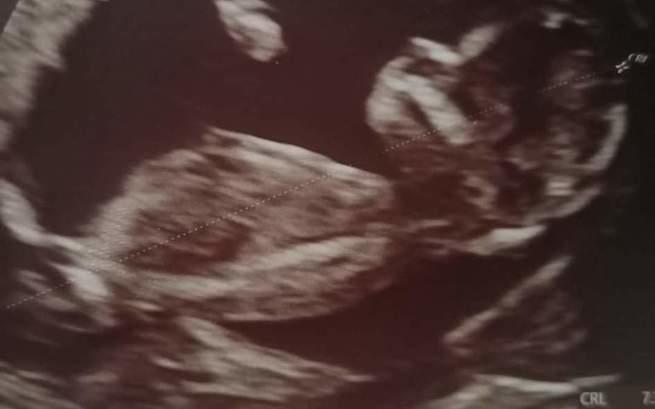

W szpitalu specjalistycznym w Łodzi, w którym ma się odbyć poród, było robione echo serca płodu na początku 34 tygodnia ciąży. Potwierdzona została wada serca pod postacią całkowitego przełożenia wielkich naczyń z małym podpłucnym ubytkiem przegrody komorowej.

Ustawienie pnia płucnego wskazuje, że dziecko najprawdopodobniej będzie miało zespół Taussig Binga – wadę o podpłucnej lokalizacji ubytku międzykomorowego z przemieszczeniem aorty do przodu względem tętnicy płucnej. Ze względu na powagę wad serca – jest to złożona sinicza wada serca...

U naszego nienarodzonego dziecka stwierdzono poważne, złożone wady serca. Już w 12 tygodniu na badaniach prenatalnych usłyszałam gorzkie słowa z ust lekarzy… Potem wiele badań, echo serca malutkiej i potwierdzenie – dwuujściowa prawa komora serduszka z ubytkiem w przegrodzie międzykomorowej.